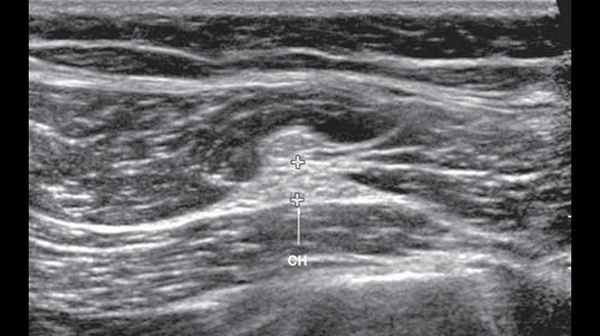

УЗИ седалищного нерва проводили в положении пациента лежа на животе. Седалищный нерв визуализировали дистальнее седалищного бугра в промежутке под сухожилиями полуперепончатой и полусухожильной мышц и длинной головкой бицепса на протяжении от ягодичной области до места деления на большеберцовый и общий малоберцовый нервы. Исследование проводили в поперечной и продольной плоскости сканирования (рис. 6, 7).

Рис. 6. В-режим. Исследование левого седалищного нерва в поперечной плоскости сканирования в верхней трети задней поверхности бедра: СН - седалищный нерв.